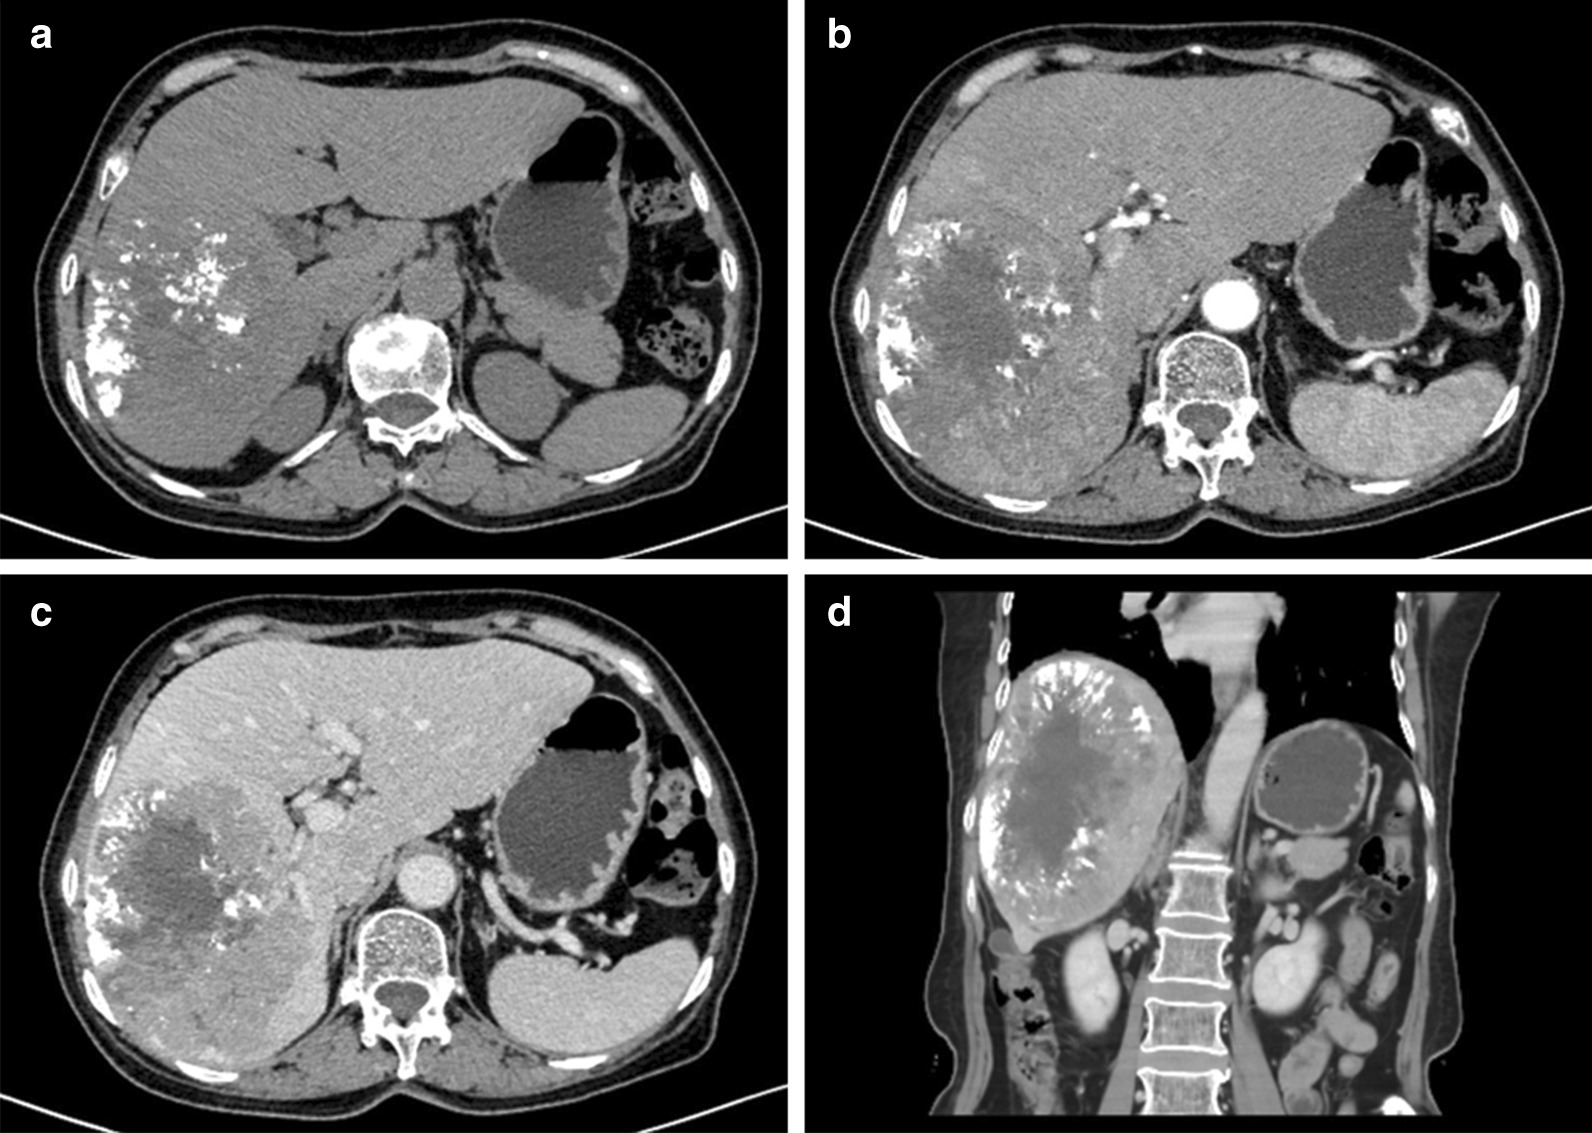

TACE is the most widely used primary treatment for unresectable HCC, and was the recommended first-line therapy for patient with intermediate-stage disease [1]. Liver resection remains the curative for various liver malignancies [2]. Currently the extent of liver resection/future liver remnants volume has been shown to most consistently and decisively determine the liver regeneration [3]. Truly some centers for radiation segmentectomy has also shown the encouraging results using selective internal radiation therapy(SIRT) as an alternative to curative therapies, but it is not supported by guidelines due to a lack of solid evidence. Therefore, considering the massive entity, the patient first underwent TACE to minimize the size of the mass. Approximately one and a half months later, a repeat abdominal enhanced CT was performed, showing the changes after TACE (Fig. 2). Additionally, the gallbladder lesion became more obvious (Fig. 3).

Fig. 2.

Abdominal CT images after TACE to observe the hepatoma. a Plain scan, b arterial phase, c venous phase, d coronal plane

Fig. 3.

Abdominal CT images after TACE to observe the gallbladder mainly. a Arterial phase (white arrow indicating nodular thickening in the gallbladder wall), b venous phase